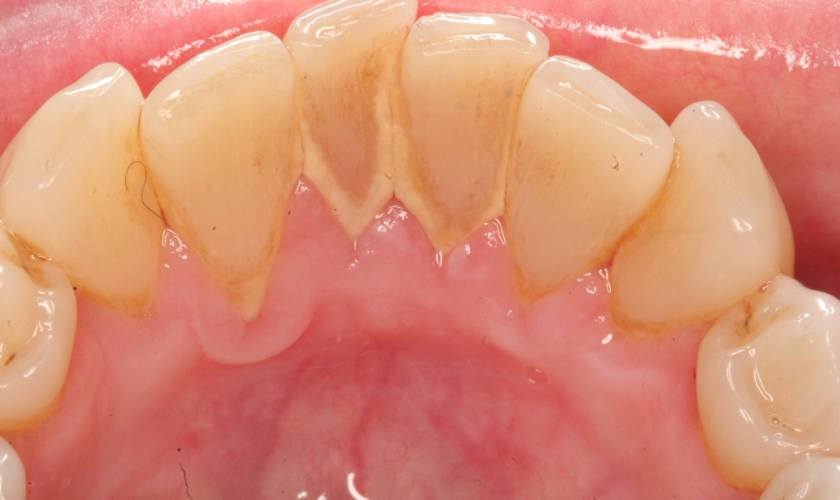

Vôi răng là kết quả của quá trình mảng bám, cặn vụn bị đông cứng bởi vi khuẩn, muối muối canxi carbonat và calcium phosphate có trong nước bọt của chúng ta. Vôi răng có màu vàng, nâu và bám rất chắc trên răng, kẽ răng và bên trong đường viền nướu.

- Vôi răng có màu vàng, nâu khiến răng bị nhiễm màu theo thời gian, ảnh hưởng đến thẩm mỹ, gây tâm lý tự ti